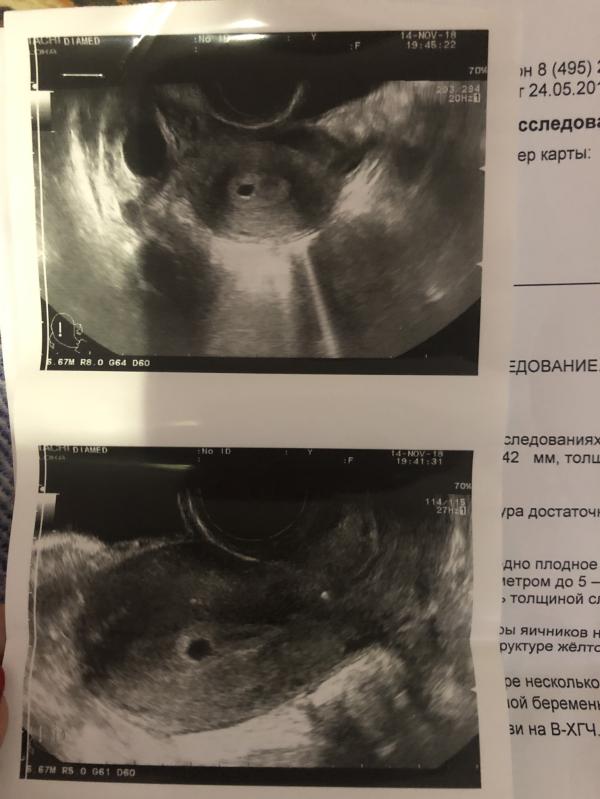

Пошла я на узи, т.к. тянущие боли внизу живота, и мне узист выдаёт, похоже беременность😳

И он мне говорит, вижу плодное яйцо, внутриматочная беременность, я ещё сильнее в шоке, срок 2-3 недели!

Сдала кровь на b-хгч, результат показал <1, беременности нет

Сделала даже сегодня тест, раз плодное яйцо есть, должен по логике тест показать положительно, но нет и тут тоже беременности нет

Что это тогда, если не плодное яйцо?

может ли быть ошибочное узи?

Прикладываю фото

Может то что 2-3 недели срок маленький и была поздняя овуляция или ранняя и тест не показывает и хгч как то странно! Но это реально плодное яйцо

Может киста? На таком сроке плодное яйцо уже разглядели прям фантастика

Это узи мое второе, первое было 31.10, на 5 день месячных, ничего не сказали, сказали миома есть маленькая, кист никаких не было

@nadushenka только хотела написать, не вижу эмбриона, только плодное яйцо. А ХГЧ вырабатывается оболочкой эмбриона! А не плодным яйцом. Надо пересдать ХГЧ попозже.